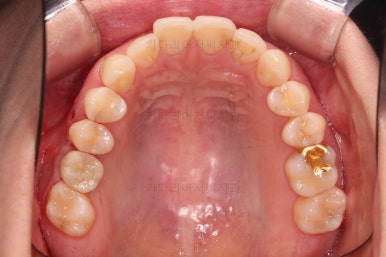

이번 환자분이 선택한 앞니 부분교정 장치는 MTA라는 장치인데요.

부분교정에 좀 더 특화된 부피가 작고 심미적인 장치입니다.

물론 철사는 들어가고요.

어금니쪽은 쓰러진 어금니를 원위치 시키기 위해서 미니스크류를 식립하여 준비작업을 해줍니다.

어금니 위치 조절을 계속 해주고요.

아래 앞니는 부분교정에 필수인 치간삭제를 병행하면서 많이 가지런해지고 있습니다.

아랫니 부분교정이 끝났고요.

어금니도 원위치로 많이 갔네요.